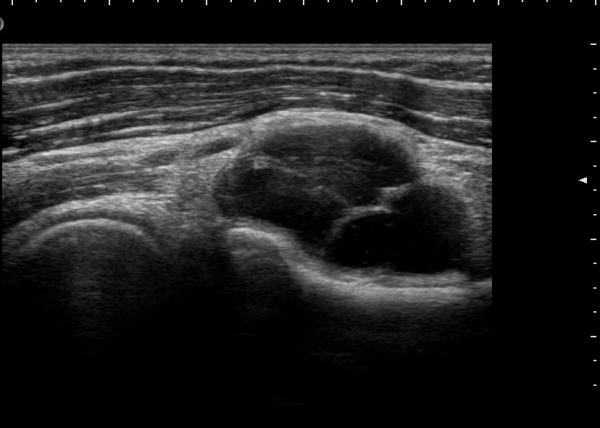

ÃÊÀ½ÆÄ °Ë»ç

¿ä°ñ½Å°æÀÇ Èİñ°£½Å°æºÐÁö Ⱦ´Ü¸é°Ë»ç¿¡¼­ ¼ÒµÎ Ç¥Ãþ »ó¿Ï±Ù°ú »ó¿Ï¿ä°ñ±Ù »çÀÌ¿¡¼­

½Å°æ ºÐÁö°¡ Àß °üÂûµÈ´Ù(±×¸² 1).